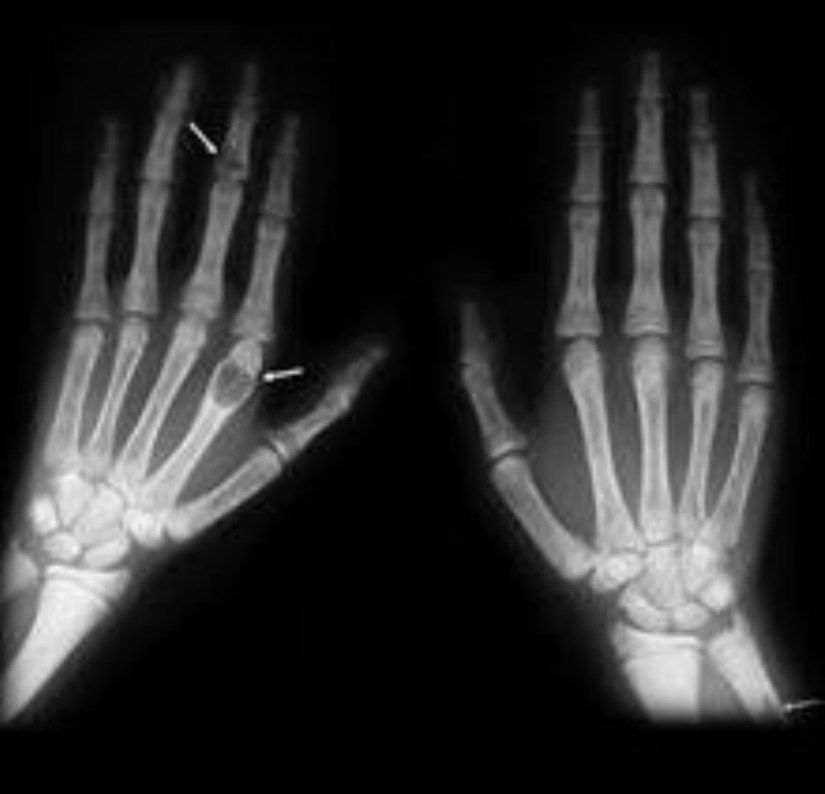

👉An extreme form of parathyroid bone disease termed osteitis fibrosa cystica is characterised by significant loss of bone density, development of bone cysts and brown tumors (shown below), skeletal deformity, bone pain, and a propensity for pathologic fractures.